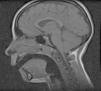

El hemograma y la bioquímica sérica con amonio, lactato, hormonas tiroideas, homocisteína y creaticinasa fueron normales, al igual que la radiografía de tórax. En la resonancia magnética craneal se observó un discreto descenso de las amígdalas cerebelosas (fig. 1). La espirometría no resultó valorable por falta de colaboración.

La MC-I viene definida por la herniación caudal de las amígdalas cerebelosas por debajo del foramen magno, lo que puede interferir con el correcto funcionamiento del tronco del encéfalo y la porción superior de la médula espinal, afectándose las estructuras del sueño, los pares craneales bajos y los centros cardiorrespiratorios.